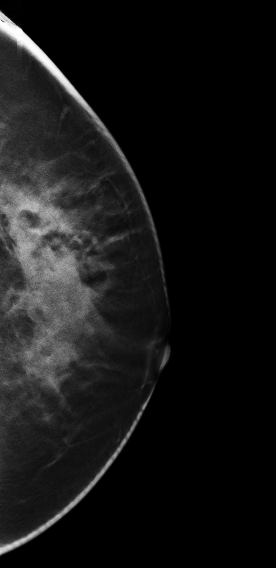

DBT图像:

放大图像:

影像描述: 在2D常规图像上并没有发现明显异常,只是感觉左乳外上象限局部不对称腺体结构有些乱,可见散在颗粒样钙化,在V-Preview(合成2D)也没有发现明显异常改变,但在3D-plane图像上我们可以明确左乳外上象限局部腺体结构紊乱,内见多颗钙化(由于医院才刚刚开展这项新技术检查医生在诊断阅片上经验不足及固有的2D阅片模式忽略了动态连续观察病灶,最后诊断为良性病变),3D动态连续薄层放大观察钙化灶我们会发现病变区钙化灶呈多形性,串珠样排列,并不是2D 和V-Preview显示的颗粒样良性钙化表现 影像诊断: 左乳外上不对称致密,考虑良性病变,BI-RADS 2级 病例点评: 病理证实:左乳导管原位癌。由此可见DBT在观察细小钙化的形态上分布上优于常规2D和V-Preview(合成2D)图像。